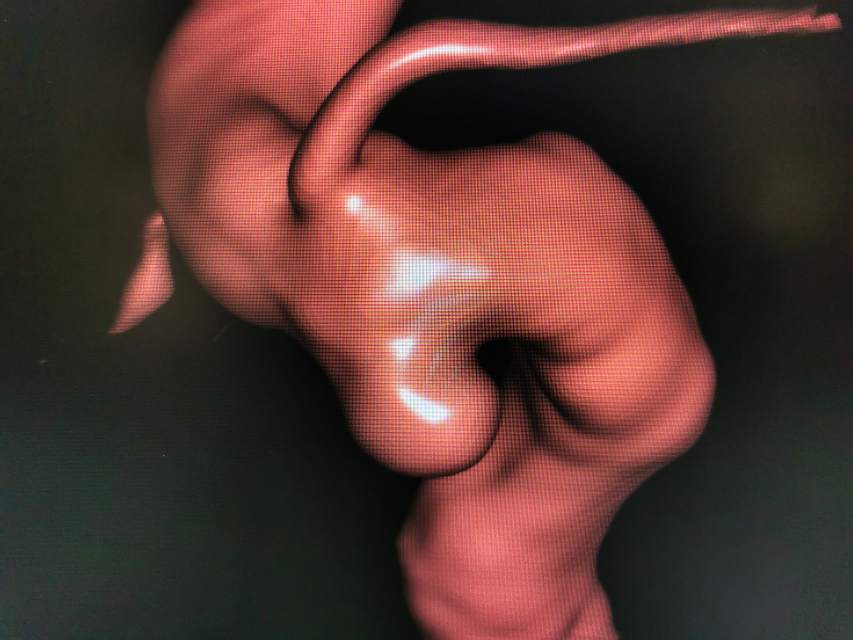

Jailing技术治疗床突旁未破裂动脉瘤